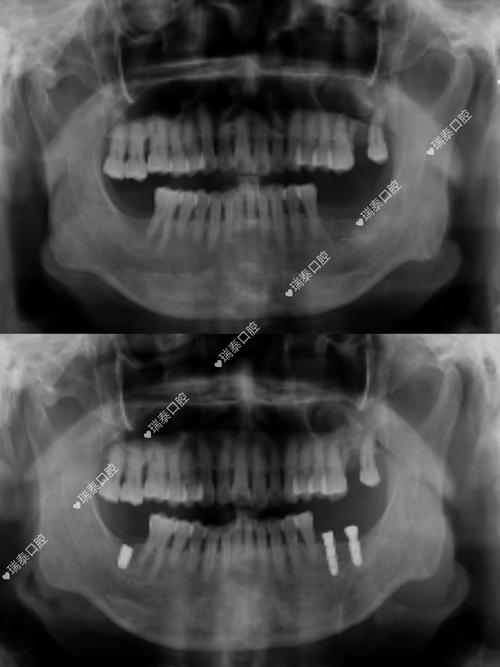

种牙前是否需要拍片,是许多准备接受种植牙手术的患者关心的问题,从临床实践来看,拍片不仅是必要的,更是保障种植牙成功和安全的关键环节,种植牙手术并非简单的“种螺丝”,而是需要通过精准的影像学检查,全面了解患者的口腔内部情况,从而制定个性化的治疗方案,避免术中损伤重要解剖结构,确保种植体能够长期稳定存在于牙槽骨中。

种植牙的核心原理是将人工种植体(相当于人工牙根)植入牙槽骨内,通过骨结合实现与骨组织的融合,再在上方安装牙冠,恢复牙齿的形态与功能,这一过程对牙槽骨的条件、周围解剖结构的要求极高,而拍片正是获取这些关键信息的“眼睛”。

评估牙槽骨的质量与数量是拍片的核心目的之一,牙槽骨的高度、宽度、密度直接影响种植体的稳定性和长期成功率,缺牙后牙槽骨会逐渐萎缩,若骨量不足,可能需要植骨或上颌窦提升等额外手术;若骨密度过低(如骨质疏松严重),种植体与骨的结合效率会降低,甚至导致失败,通过影像学检查,医生可以准确测量骨量,判断是否具备直接种植的条件,或需要何种骨增量方案。

CBCT因三维成像的优势,已成为现代种植牙术前检查的重要手段,对于上颌后牙区种植,CBCT能清晰显示上颌窦底的位置和骨壁厚度,判断是否需要上颌窦内提升或外提升;对于下颌后牙区,可精准标记下牙槽神经管的位置,避免种植体进入神经管。